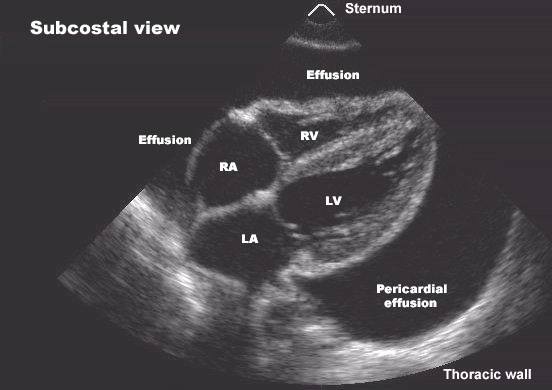

Pericardial effusion can be caused by pericarditis, malignancy, tuberculosis, uremia, hypothyroidism, trauma, autoimmune diseases, or post-cardiac surgery.

Pericardial effusion progresses to cardiac tamponade when intrapericardial pressure rises enough to impair cardiac filling, leading to hypotension, elevated jugular venous pressure, and reduced cardiac output.

Key signs include hypotension, elevated jugular venous pressure, tachycardia, muffled heart sounds, and pulsus paradoxus. Echocardiography confirms the diagnosis.

The definitive treatment of cardiac tamponade is urgent pericardiocentesis to relieve pressure on the heart. Supportive measures are only temporary and should not delay drainage.